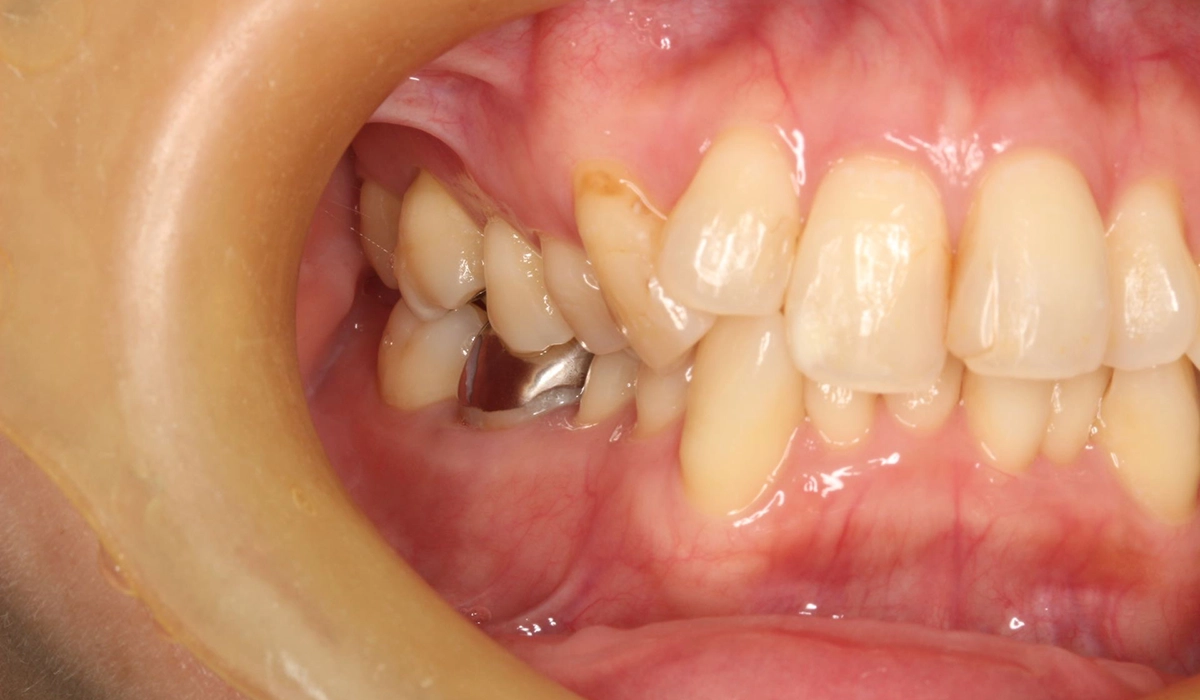

術前:右側

| 治療内容 | 患者様は全体的な歯のがたつきを気にされており、矯正検査後Ⅰ級叢生と診断。抜歯適応症例だが患者希望により歯肉退縮を許容したうえで非抜歯で仕上げている。 |

| リスク・副作用 | ・協力度(装着時間、来院、顎間ゴムの使用など)が治療期間や結果に影響します。 ・事前のシミュレーションのゴールを目指し歯を移動させていく治療法ですが、歯の動きには個人差があるため確実に結果を保証するものではありません。 ・食事に時間がかかり、歯ごたえのあるものが食べにくくなります。 ・歯の移動に伴う痛みや装置による口内炎、関節音、閉口障害、頭痛、耳鳴り、筋の硬直などが生じることがあります。 ・歯の動きに伴い、歯肉退縮や歯根吸収が生じることがあります。 ・ブラックトライアングル(三角形の隙間)ができることがあります。 ・歯の動かし方によっては詰め物やかぶせ物を外す可能性があります。外した場合は矯正終了まで仮の材料を入れ、終了後に新たに作り直す必要があります。 |